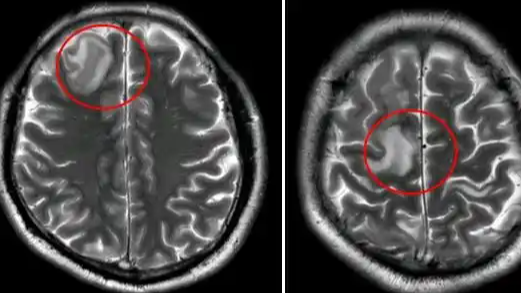

感冒后想通过汗蒸“排毒”,34岁男子两天内汗蒸三次,出现头晕手抖、行走不稳症状,被确诊为危险的脑静脉窦血栓。广东三九脑科医院神经内二科医生介绍,这是一种罕见却危险的中风。起因是汗蒸脱水导致血液浓缩,脑静脉系统“排水”异常,诱发脑静脉窦血栓。